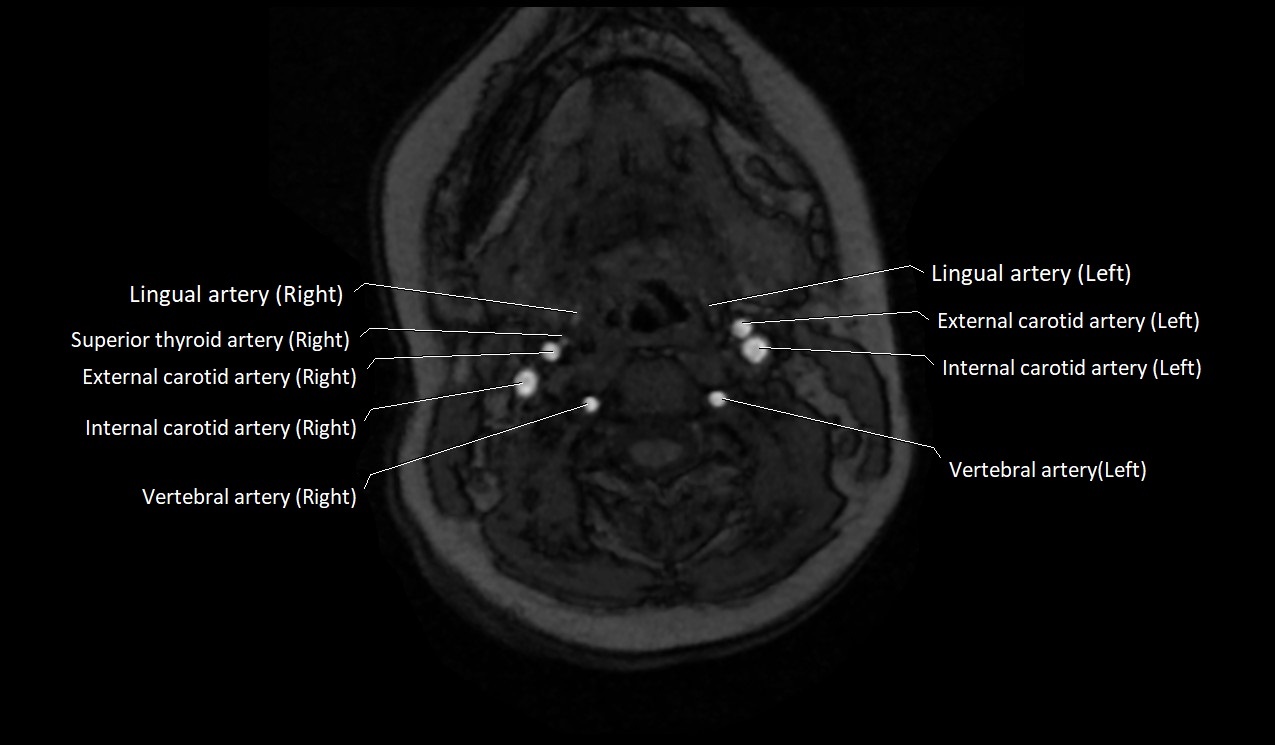

MRI Appearance:

• T1-Weighted Images:

• Appears as a tubular, hypointense (dark) structure relative to muscle

• May show flow void if the blood flow is fast

• T2-Weighted Images:

• Typically hypointense or isointense to muscle, but can be hyperintense if slow flow or stasis is present